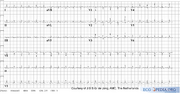

| 11:17, 24 September 2007 | PulsusAlternans.png (file) |  |

1.27 MB | Vdbilt | An ECG of a 40 year old man with Kahlers' disease and tamponade. Note the electrical alternans in the precordial leads and the microvoltages in the extremity leads | 1 |